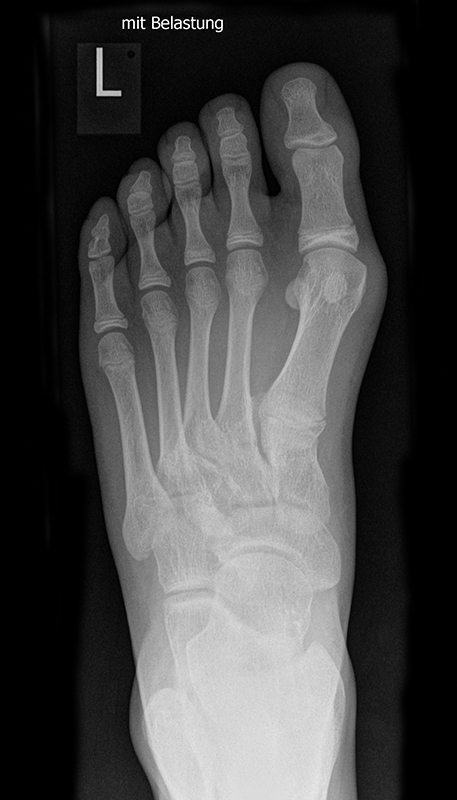

Die folgenden Bilder zeigen die belastete Röntgenaufnahmen des linken Fußes einer jungen Patientin zu Beginn der Therapie und nach 6 Monaten Training. Erkennbar ist die höhere muskuläre Verspannung des Fußes mit verbesserter Stellung der milden Hallux valgus Deformität.